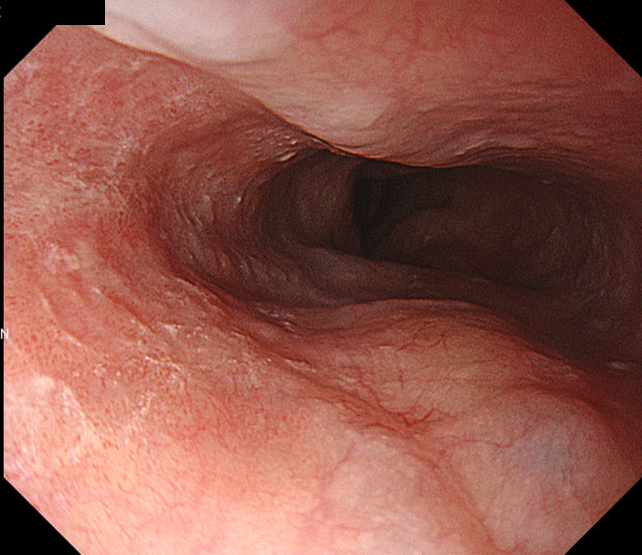

• NBI+TXI観察(近景)

切替前 NBI強調設定:B8

NBI+TXIレベル:中

図3 TXI 近接食道病変

腫瘍部のドット状血管を非拡大で明瞭に視認することができる。